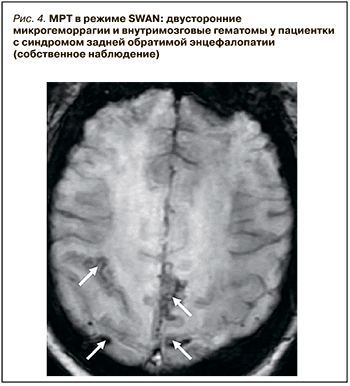

Активное применение КТ и МРТ позволило расширить представления о нейровизуализационных особенностях СЗОЭ. Так, к настоящему времени установлена возможность вовлечения в патологический процесс не только белого (лейкоэнцефалопатия), но и серого вещества головного мозга. Кроме классической локализации, изменения при СЗОЭ могут быть и в других отделах больших полушарий, подкорковых структурах, стволе и мозжечке (рис. 3) [10–12]. Значительно реже наблюдается односторонняя или асимметричная локализация СЗОЭ [13, 14]. Возможно также изолированное поражение ствола головного мозга или подкорковых структур без вовлечения классических зон [15, 16]. Кроме этого, показана возможность развития цитотоксического отека и ишемических изменений [9], микрокровоизлияний, внутримозговых и субарахноидальных кровоизлияний (рис. 4) [17]. Согласно данным Liman T.G. et al. [18], существует положительная связь между обширностью вазогенного отека головного мозга и вероятностью развития геморрагических осложнений.

Быстрый и значительный подъем АД приводит к нарушению компенсаторных вазоконстрикторных механизмов и вызывает пассивное растяжение мелких церебральных сосудов [22, 23]. Это способствует повышению проницаемости ГЭБ и развитию вазогенного отека головного мозга [28]. При этом имеется положительная корреляция между быстротой и степенью подъема АД и повышением проницаемости ГЭБ [29]. В тяжелых случаях ГЭБ становится проницаем и для форменных элементов крови, что влечет за собой кровоизлияния.